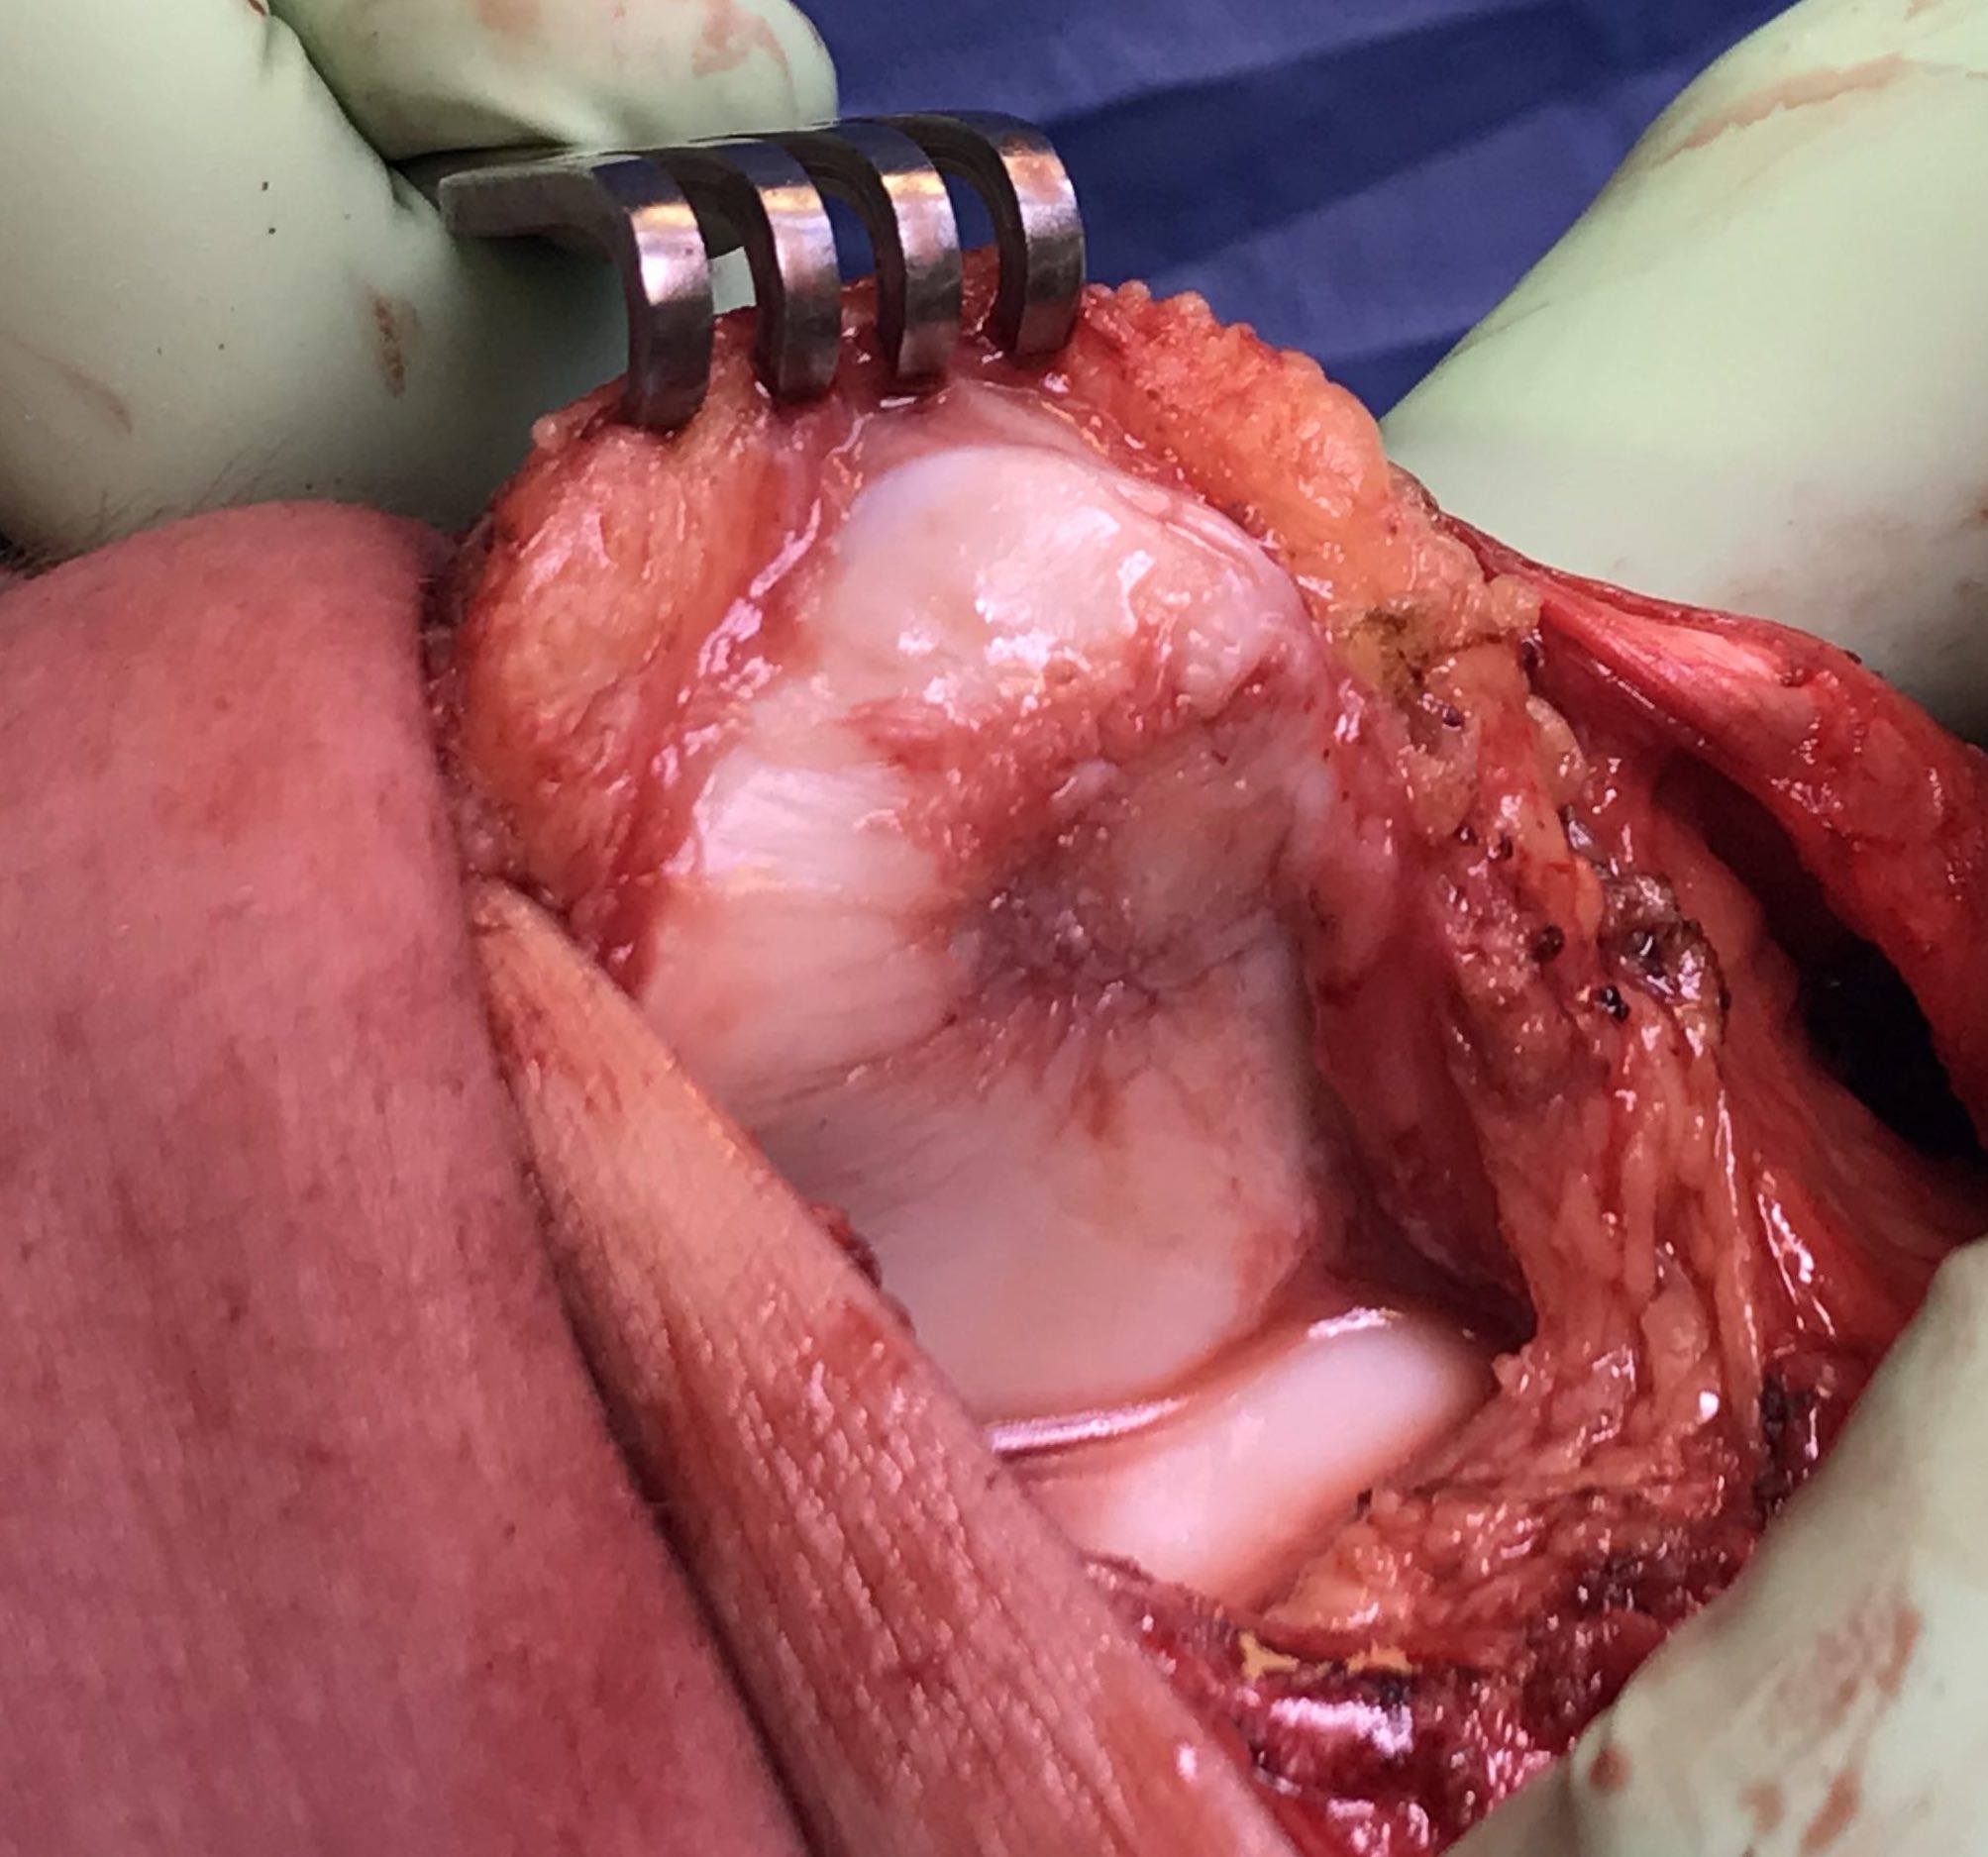

Implantation

- medial or lateral parapatellar approach

- create sharp stable margins

- curette base

- control bleeding with adrenalin soaked gauze to avoid graft displacement

- size defect with foil - graft cannot be prominent or will displace with ROM

- secure with fibrin glue / Tisseal

- ensure graft stability with knee range of motion